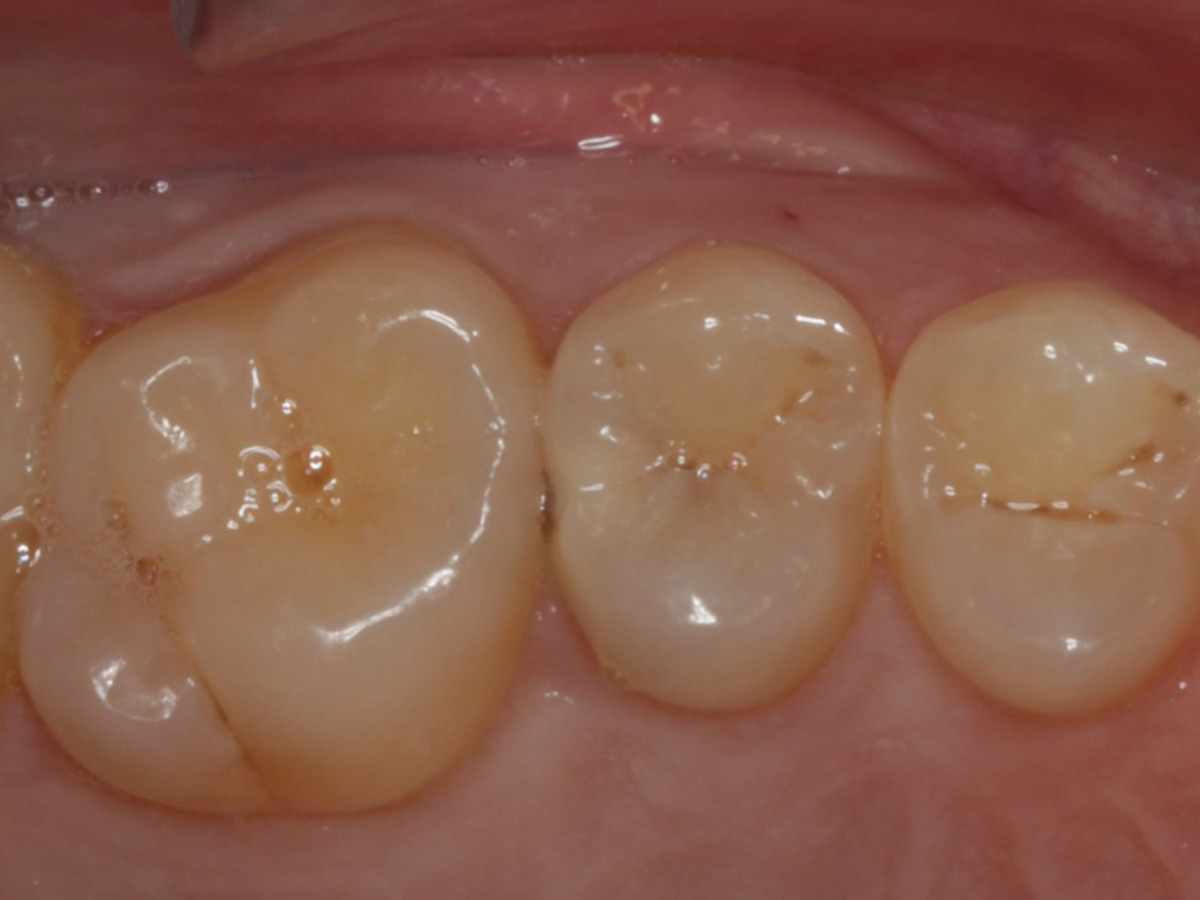

Abbildung 18

Fertige Restauration